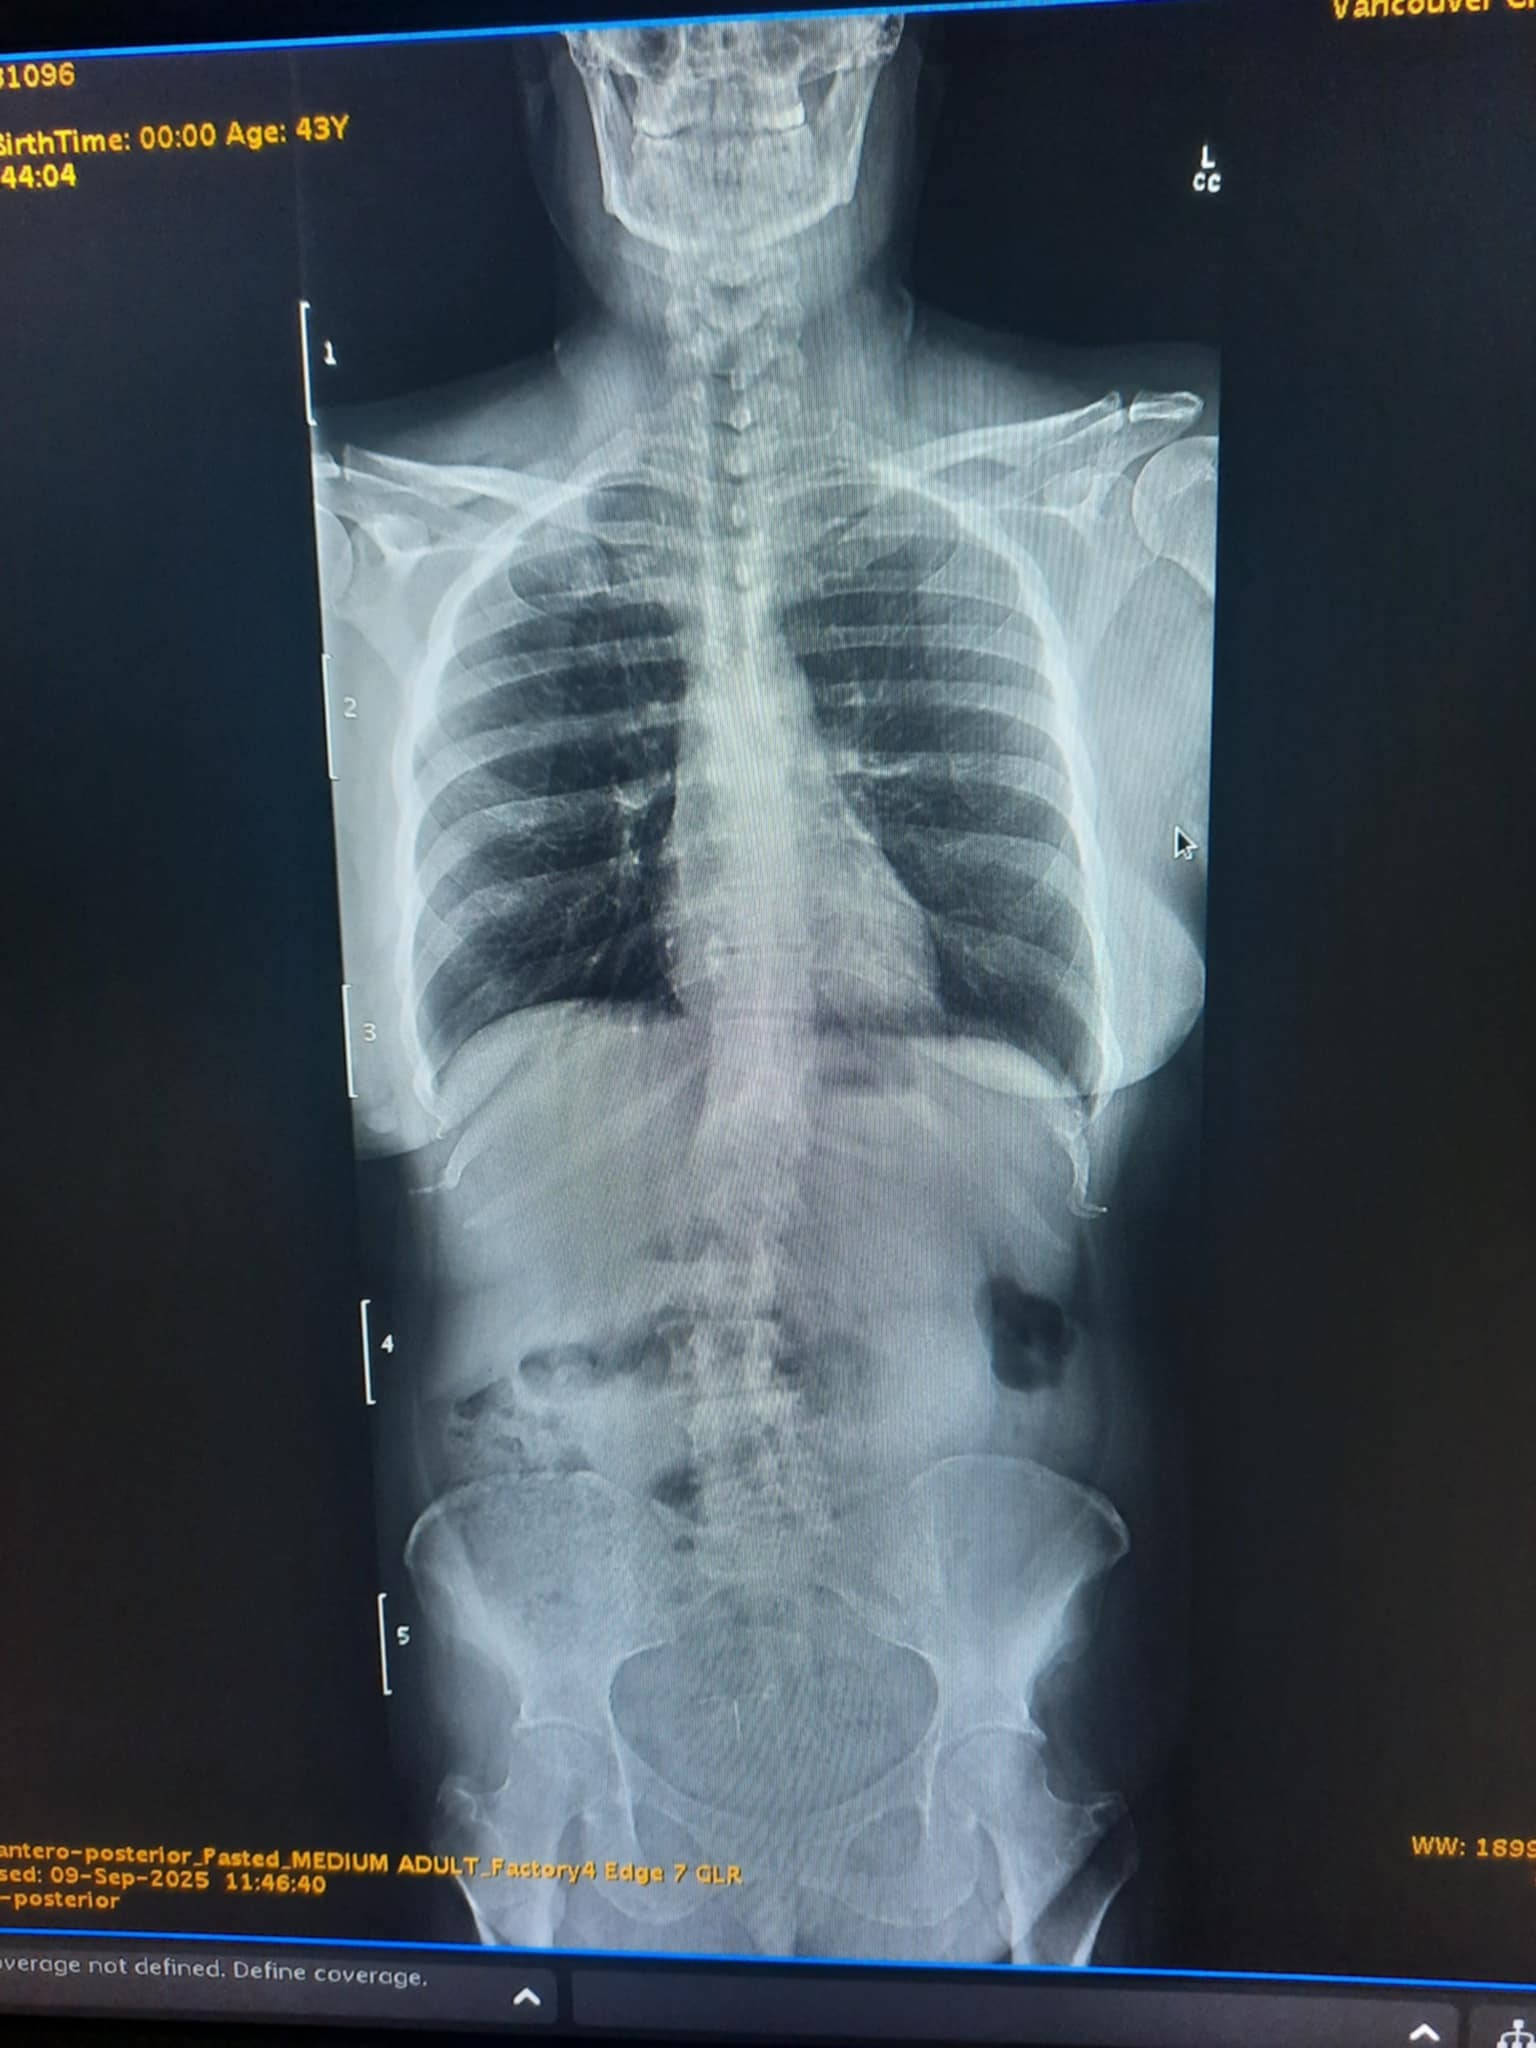

Because so many of us in the DOTK community are believing God for healing miracles, I rarely do this unless God leads me to. In this case, I’m led of the Lord to share an urgent prayer request for our sister, Kristin. She is in need of a healing miracle of God. I have been in communication with her and though her faith is strong, her pain and suffering is great from her spinal condition. She has undergone surgery for her spine but while in post-surgery, she suffered abuse and neglect while in hospital care, bed sores, clots, and swelling. She needs our prayers, and for her sisters around the world to “climb the top of the house, open the roof and let her down to Jesus”

Thank you for praying for me. I will speak His Truths and Promises over my life. Healing is my portion. These DVTs and blood clots will flee in the name of Jesus! Father, remove the pulmonary embolism in my right lung in the name of Jesus. I believe and receive Your restorative healing in my spine and I will walk again in the name of Jesus. I am standing on Isaiah 40:31! Hallelujah! Tehillah! Amen. Thank You, Lord! Thank you for standing in agreement and lifting me before the throne! Our prayers are like incense, a pleasing aroma to the One Who sits there!

Praise Report: God healed me. The pulmonary embolism in my right lung is gone!! Hallelujah!